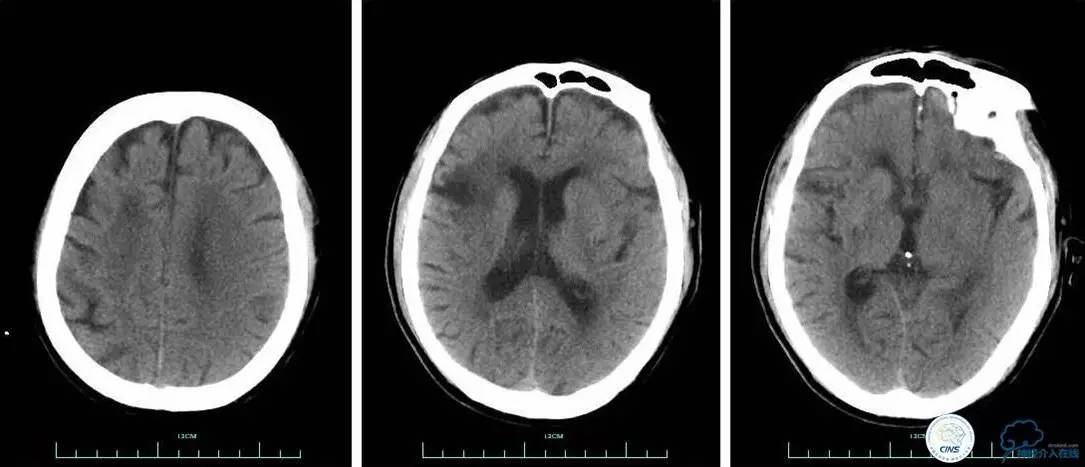

▼术前头颅CT平扫:

辅助检查:血常规、生化、凝血功能未见明显异常,心电图:心房颤动,ST-T改变;头颅CT平扫未见明显出血。

▼术后头颅CT复查:未见明显出血,左侧脑室旁可见少许低密度病灶。